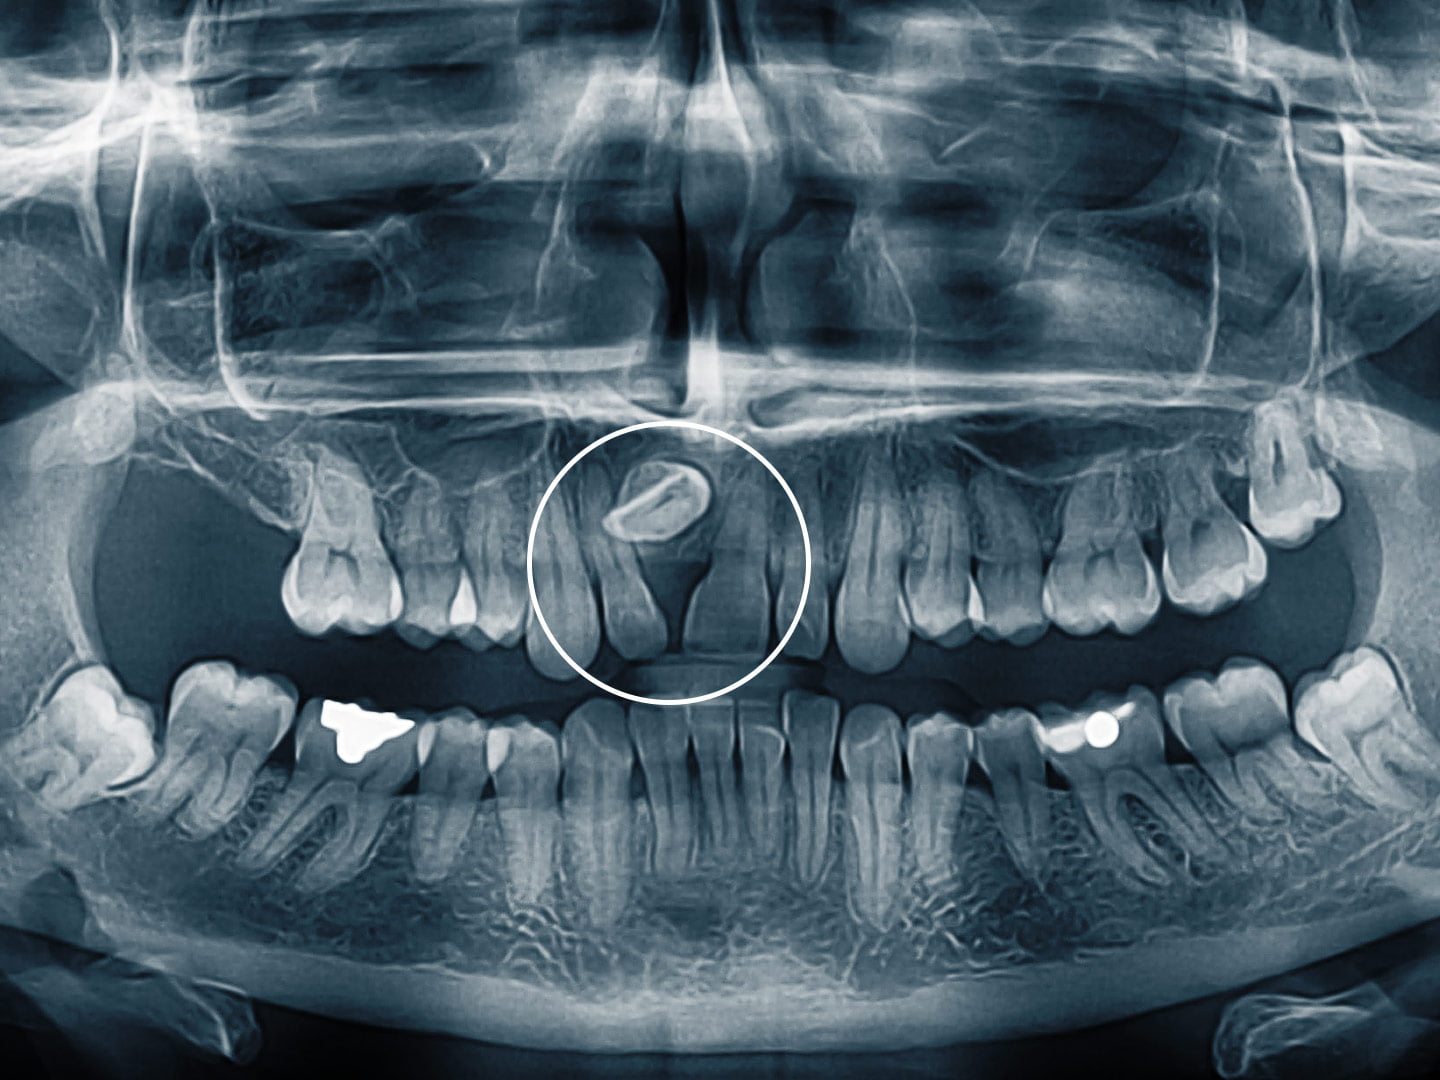

„Több fogászati gondom is volt. A teljes fogsoromra nyomást gyakorló bölcsességfogak, szuvasodások, illetve egy rendellenesség: az egyik frontfogam bent rekedt a felső állcsontban, rossz pozícióban; emiatt komoly hézag volt a frontfogaim között.

A főorvos úr a röntgenfelvételt alaposan tanulmányozta, a fogsoromat pedig hosszasan vizsgálta. Kiderült, hogy mind a négy bölcsességfogamat ki kell húzni, mert helyhiány miatt nyomják a fogsoromat; ez volt az oka az állandó nyomásérzetnek a számban. Ez a diagnózis azonban eltörpült a jó hír mellett! A gondos vizsgálat után ugyanis a főorvos úr megnyugtatott, hogy a saját fogaimra helyezett cirkónium híddal – ami egy teljesen fémmentes pótlás – kivitelezhető a mosolyszépítő beavatkozás, orvosolható a hézag okozta esztétikai probléma. Juj, de boldog voltam!